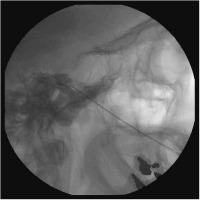

Glyzerinrhizolyse - Cavum Meckeli - Zisterna trigemini

Abbildung 6: Glyzerinrhizolyse: Röntgenaufnahme der Schädelbasis seitlich. Nadelspitze im Kontrastmittelfüllung der Zisterna trigemini.

Keywords: Cavum MeckeliGlyzerinrhizolyseNeurochirurgieRöntgenZisterna trigemini